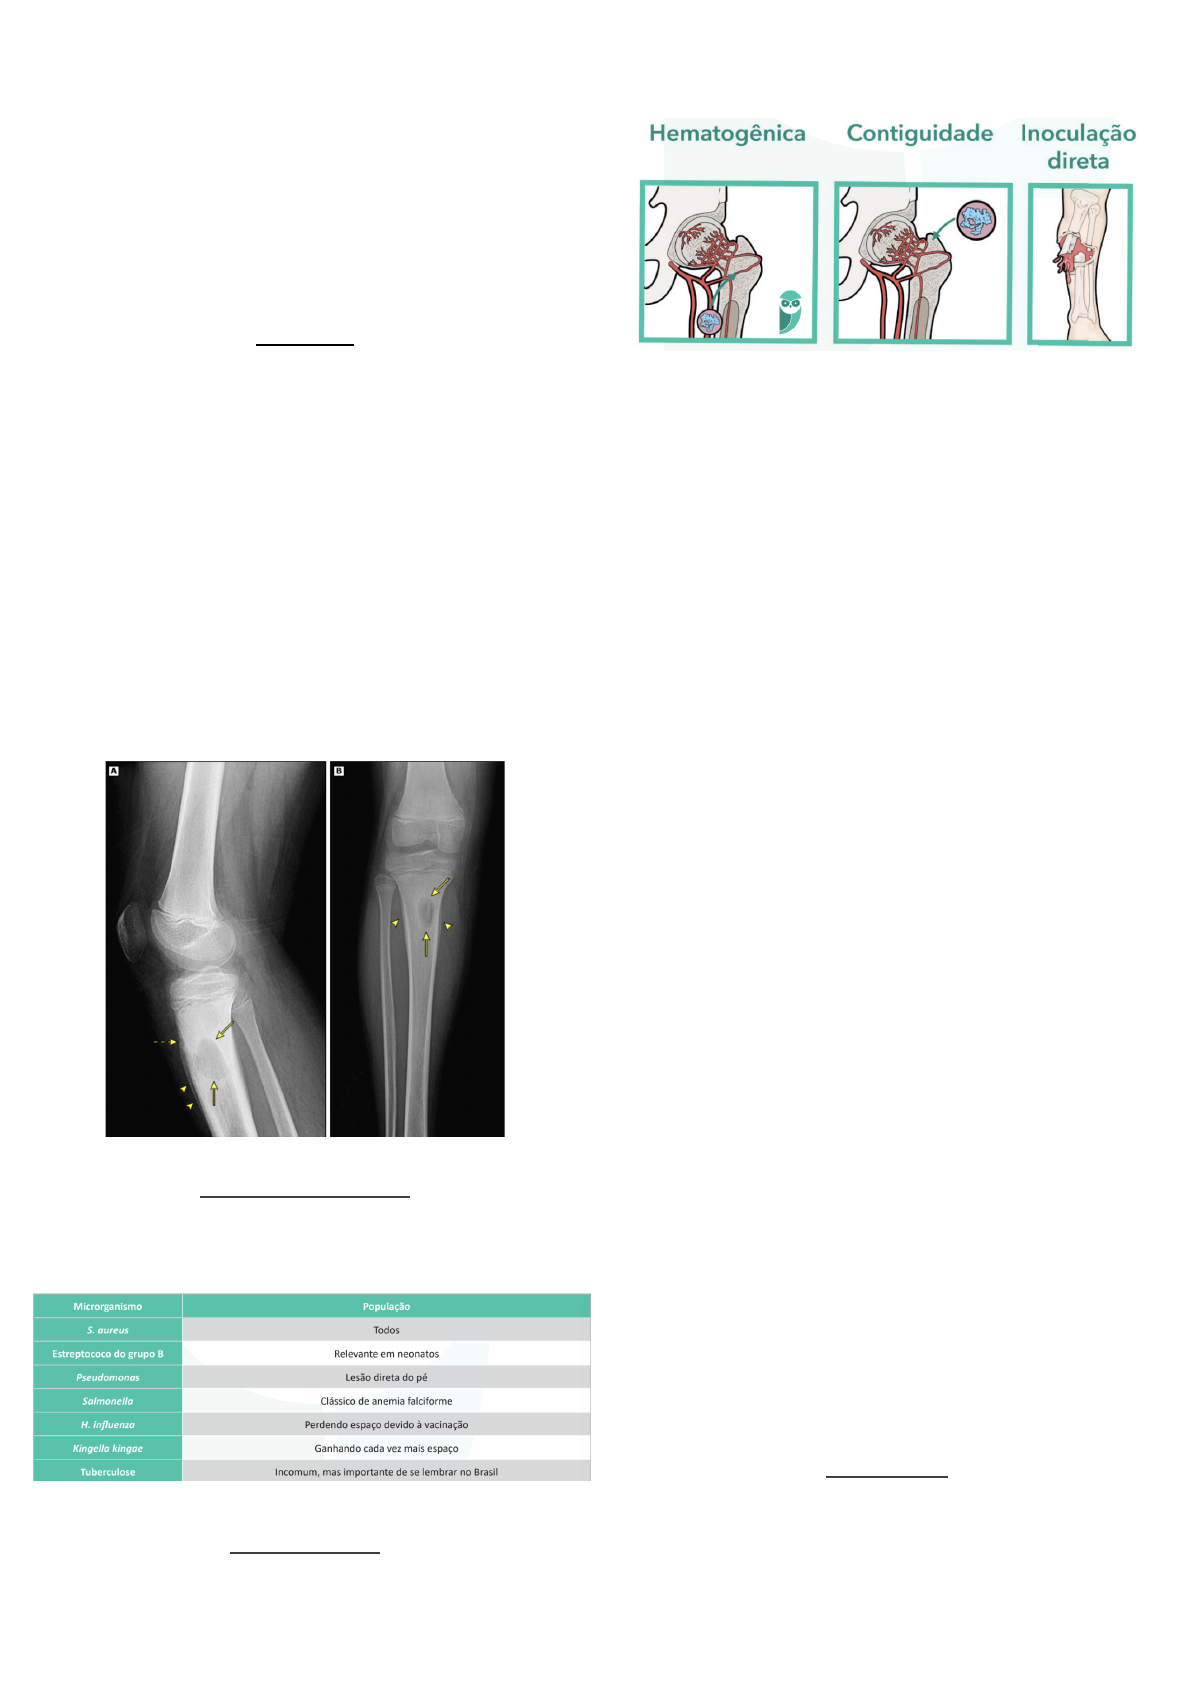

- As osteomielites podem ter origem: (1) hematogênica;

(2) por contiguidade; ou (3) por inoculação direta.

- Radiograficamente, a maioria dos pacientes apresenta

sequestros ósseos, além de uma alteração denominada

involucrum (camadas sobrepostas de osso neoformado

que revestem o osso subjacente).

- Exames de imagem

- Ressonância: alterações muito mais detalhistas e

apuradas.

- Radiografia: alterações minimamente visíveis, pois as

alterações só aparecem uma semana após a infecção.